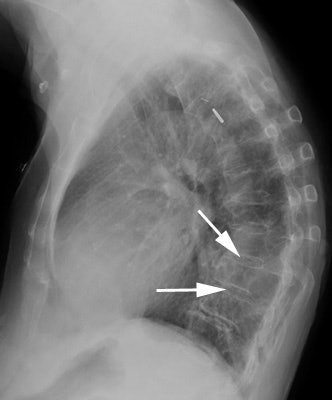

On CT the lesion appears as a homogeneous, water density paravertebral mass which may enlarge the neural foramina, cause posterior vertebral scalloping, or produce a scoliosis (found in 50% of cases- the meningocele is near the apex of the deformity on the convex side). The lesion does not enhance with contrast. Myelography can be used to demonstrate communication with the subarachnoid space. On MRI, the signal intensity of the fluid within the meningocele is identical to that of CSF.Lateral thoracic meningocele: The patient below presented with back pain. The CXR demonstrated a large posterior mediastinal mass. If you look carefully at the lateral view you can see that the neural foramina at the level of the lesion is expanded. CT scan demonstrated bilateral lateral thoracic meningoceles- larger on the right, with neural foramina expansion and posterior vertebral scalloping. MR demonstrates signal intensity identical to CSF. |